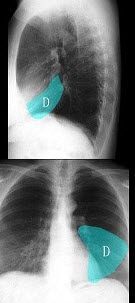

42、单项选择题

男,46岁,双髋部疼痛,实验室检查血钙升高,尿本周蛋白(+),结合图像,最可能的诊断是()

A.骨髓瘤

B.骨质疏松症

C.骨转移瘤

D.骨囊肿

E.针状骨膜反应

男,20岁,胸闷、低热1月余,突然咯血,X线检查如图,最可能的诊断是()

A.肺结核(Ⅰ型)伴右侧胸腔积液

B.肺结核(Ⅲ型)伴右侧胸腔积液

C.肺结核(Ⅱ型)伴右侧肺不张

D.肺结核(Ⅲ型)伴右侧肺不张

E.肺转移瘤伴右侧肺不张